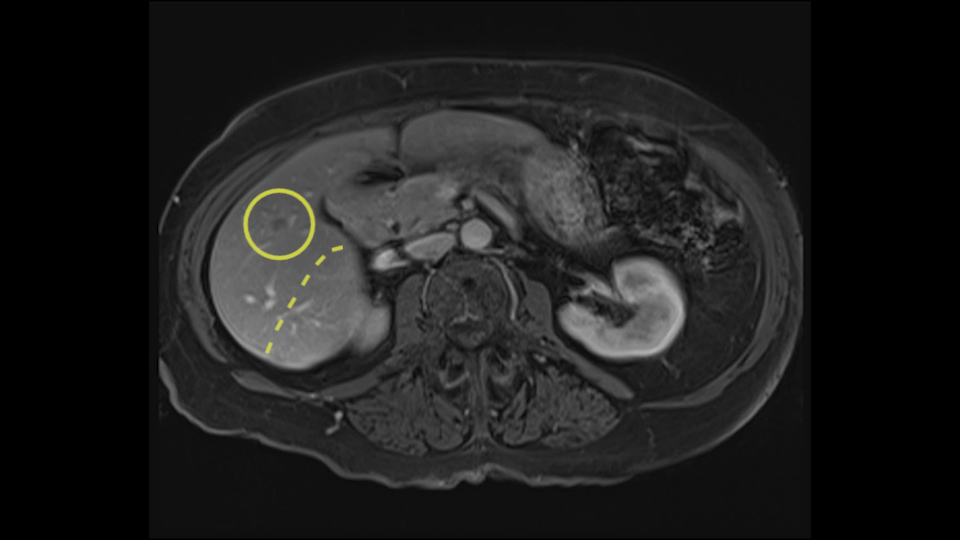

The third issue for this patient is that in Segment 7, I notice that there is intrahepatic ductal dilatation due to a small tumor causing obstruction. Now this tumor is not well-visualized on the most recent CT scan but I want to carefully evaluate the bile duct, where the obstruction is, so at the time of surgery I can be sure to remove the affected bile duct as well as the small tumor that is causing the ductal dilatation.

My name is Steven Gallinger, I’m a professor of surgery at the University of Toronto and an HPB surgeon at the University Health Network. I’ve been asked to comment on this case and discuss preoperative planning, potential slowing down moments. It’s an interesting 65-year old woman with right sided colon cancer and synchronous liver metastases: small metastases in the right lobe of the liver and she had the primary tumor resected and then underwent neoadjuvant chemotherapy for her small liver metastases in Segments 4, 5, 6 and 7. The distribution of the metastases is interesting. They are small lesions, but the interesting additional feature is isolated segmental dilatation of the Segment 7 bile duct which suggests an intrabiliary metastasis somewhere near the origin of the main Segment 7 duct. Because I can trace it close to the porta [hepatis], I would assume that it’s pretty close to the bifurcation of the main right sided bile ducts but I can’t actually see the actual tumor. It’s really just presumptive.

She underwent neo-adjuvant chemotherapy and then had a series of additional investigations and the one that I’m focusing on in more finer detail is an MRI with Primovist and I’ve had the benefit of looking at the report. The main issues are in Segments 5,6, and 7. Three small metastases that remain and the radiologist also comments on the lack of biliary dilatation which was present before; implying that the intrabiliary metastasis somewhere at the origin of the Segment 7 duct, has regressed or been adequately well treated with chemotherapy. That’s probably where the difficult decision making comes in the OR. So from an oncologic point of view, I would plan for a right hepatic lobectomy. The rationale would be that this would include the more peripheral Segment 5, 6, 7 metastases that are obvious but also would take care of the presumed Segment 7 intrabiliary metastasis that does not actually visualize on any of the scans but is assumed to be there with evidence of the duct dilatation which then resolved. One could argue whether we should preserve liver and ignore that duct dilatation that was there before but I think my own preference would be to resect the right lobe and that would certainly include any residual disease in that Segment 7 bile duct and moreover, coming back to do a completion right hepatic lobectomy would be difficult particularly around the porta where this metastasis is presumably still there and even if its quite small.

Finally the bile duct is divided in the liver. I can actually see this patient’s bile duct. It’s a bit dilated and she had cholecystectomy. I think we would divide the bile duct in the liver. It’s hard to anticipate from a CT scan what you’re going to see because you can’t actually see the bile duct very well on the average CT.

![[Sg7 branch]](jpg/preop_sg_moment6.jpg)

So overall I would plan to do a right hepatic lobectomy. The slowing down moments are the usual ones: carefully mobilizing the right lobe, not injuring the main hepatic veins or the vena cava, the right portal vein split, the length of the right portal vein. The rest looks very routine. The oncologic issue I’ve already decided I’m going to do a right lobe with the assumption that there is an intrabiliary metastasis somewhere near the origin of the right- the Segment 7 duct and probably close to the bifurcation of the main right bile duct so the best way to get a margin is to actually divide the right bile duct close to its origin the way you would normally do a right hepatic lobectomy.